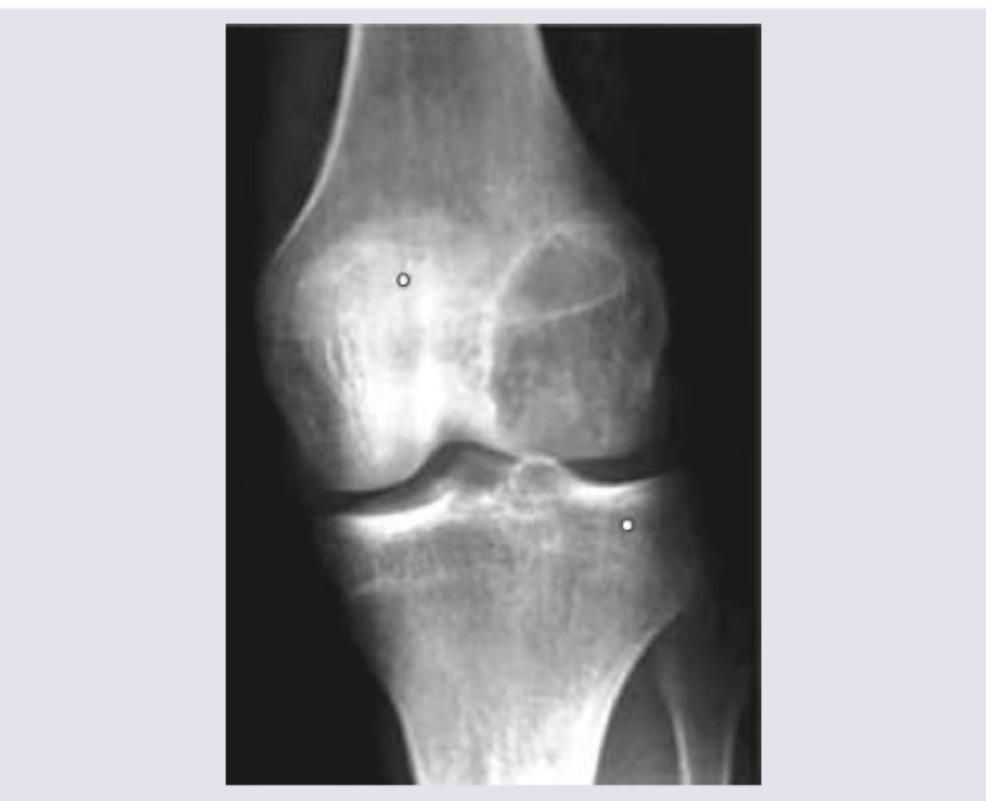

The most likely diagnosis for the lesion shown in the image is:

Explanation: ***Giant cell tumour*** - The image shows an **epiphyseal lytic lesion** in the distal femur that extends to the subchondral bone, which is characteristic of a giant cell tumour. - Giant cell tumours are usually **benign but locally aggressive**, often presenting in patients aged 20-40 years and typically involve the **epiphysis** of long bones, most commonly around the knee. *Unicameral bone cyst* - These are typically **metaphyseal lesions**, often seen in children and adolescents, and are usually **lucent** with a thin sclerotic rim. - They often present with a **"fallen fragment sign"** if there's a pathological fracture, which is not visible here. *Aneurysmal bone cyst* - An aneurysmal bone cyst is usually a **multiloculated, expansile, lytic lesion** that can be metaphyseal or diaphyseal, most commonly found in patients under 20 years old. - While it can be destructive, it typically has a **fluid-fluid level** on MRI due to blood products, which is not appreciable on this plain radiograph, and its common location differs. *Osteoid osteoma* - An osteoid osteoma is a small, benign tumour characterized by a **small radiolucent nidus** (typically less than 1.5 cm) surrounded by a large area of **sclerosis**. - It usually presents with **pain that improves with NSAIDs**, and its radiographic appearance is distinctly different from the large lytic lesion shown.

Explanation: ***Giant Cell Tumor (GCT)*** * The image shows a **lytic (lucid) lesion** located in the **epiphysis/metaphysis of the distal radius**, which is a classic presentation site for GCT. * GCTs are typically seen in individuals aged 20-40, often present with **pain, swelling, and reduced range of motion**, and can show a **soap bubble appearance** on X-ray even with cortical erosion as seen in the image. *Ewing's Sarcoma* * Ewing's Sarcoma commonly affects the **diaphysis of long bones** and may present with an **onion skin periosteal reaction**, none of which are clearly depicted. * It primarily affects children and young adults (5-20 years old), which does not align with the assumed adult presentation given the fused epiphysis. *Osteochondroma* * Osteochondromas are **bony prominences covered by cartilage** and grow **outward from the bone surface**, often away from the joint, unlike the intraosseous lytic lesion seen. * They typically appear as **pedunculated or sessile exostoses** and are benign growth plate abnormalities, not lytic lesions of the marrow cavity. *Osteoid Osteoma* * Osteoid osteomas are characterized by a **small lucent nidus** (usually <1.5 cm) surrounded by a significant margin of **sclerotic bone**, which is not seen here. * They classically cause **nocturnal pain** relieved by NSAIDs and are typically smaller than the lesion depicted, which appears expansile.